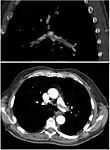

CT pulmonary angiography

CT pulmonary angiography (CTPA) is a pulmonary angiogram obtained using computed tomography (CT) with radiocontrast rather than right heart catheterization. Its advantages are that it is accurate, it is non-invasive, it is more often available, and it may identifying other lung disorders in case there is no pulmonary embolism. The accuracy and non-invasive nature of CTPA also make it advantageous for people who are pregnant.[57]

On CT scan, pulmonary emboli can be classified according to the level along the arterial tree. On CT scan, pulmonary emboli can be classified according to the level along the arterial tree.

Segmental and subsegmental pulmonary emboli on both sides Segmental and subsegmental pulmonary emboli on both sides

CT pulmonary angiography showing a "saddle embolus" at the bifurcation of the main pulmonary artery and thrombus burden in the lobar arteries on both sides. CT pulmonary angiography showing a "saddle embolus" at the bifurcation of the main pulmonary artery and thrombus burden in the lobar arteries on both sides.

Pulmonary embolism (white arrow) that has been long-standing and has caused a lung infarction (black arrow) seen as a reverse halo sign. Pulmonary embolism (white arrow) that has been long-standing and has caused a lung infarction (black arrow) seen as a reverse halo sign.

Assessing the accuracy of CT pulmonary angiography is hindered by the rapid changes in the number of rows of detectors available in multidetector CT (MDCT) machines.[58] According to a cohort study, single-slice spiral CT may help diagnose detection among people with suspected pulmonary embolism.[59] In this study, the sensitivity was 69% and specificity was 84%. In this study which had a prevalence of detection was 32%, the positive predictive value of 67.0% and negative predictive value of 85.2%. However, this study's results may be biased due to possible incorporation bias, since the CT scan was the final diagnostic tool in people with pulmonary embolism. The authors noted that a negative single slice CT scan is insufficient to rule out pulmonary embolism on its own. A separate study with a mixture of 4 slice and 16 slice scanners reported a sensitivity of 83% and a specificity of 96%, which means that it is a good test for ruling out a pulmonary embolism if it is not seen on imaging and that it is very good at confirming a pulmonary embolism is present if it is seen. This study noted that additional testing is necessary when the clinical probability is inconsistent with the imaging results.[60] CTPA is non-inferior to VQ scanning, and identifies more emboli (without necessarily improving the outcome) compared to VQ scanning.[61]